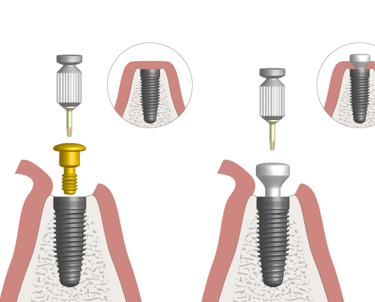

Consiste en exponer los implantes después de su integración ósea y colocar los pilares que servirán de soporte para las prótesis definitivas.

Cirugía de Conexión de implantes

Colocación de un pilar provisional para mantener el espacio y la estética mientras se espera la fabricación de la prótesis definitiva.

Colocación de Pilar de Cicatrización